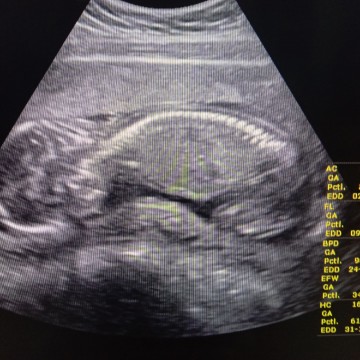

อยากเห็นใบซาวด์ทีมพฤศจิ😍

มาอวดกันเร็ววว🥰🥰 บ้านนี้13 พฤศจิ